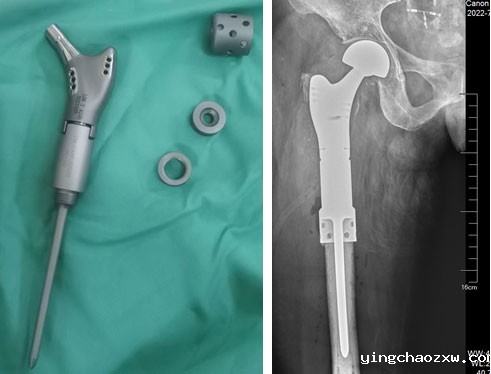

县总医院骨科团队综合研判患者病情,及时制定合理、安全、有效的治疗方案,决定为患者行右侧股骨骨肿瘤切除,肿瘤型人工髋关节置换术。因患者右股骨髓腔细小,常规人工髋关节体假体无法使用,需使用特殊假体,根据患者DR、CT,向生产厂家为患者量身定做了个性化定制型人工肿瘤髋关节假体,征对患者髓腔细,假体特别设计了个性化结合部加强套筒,确保假体强度及使用安全,术前行右下肢动脉CTA,严格评估右股骨肿瘤营养动脉血供情况,避免术中出现难以控制出血,经精心准备,在主任医师陈志强院长带领下,总医院骨科近日成功为患者实施了右侧股骨近端恶性肿瘤骨转移切除、定制肿瘤型人工髋关节置换术。手术历时2小时完成,术中患者病情平稳,术后患者疼痛疼痛消除,右下肢活动明显改善,患者的生活质量得到了极大提高,家属也十分满意。